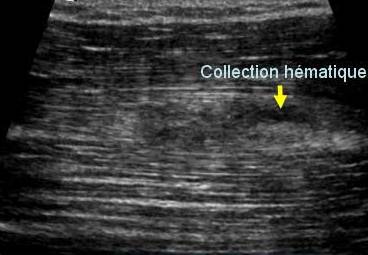

Colectie hematica

Stadiul III Rodineau

Ecografia trebuie sa precizeze, in fata unei colectii hematice, daca ea este punctionabila sau nu. O colectie este punctionabila daca ecostructura este lichidiana, necloazonata si depresibila sub sonda. In acest caz, punctia poate fi realizata sub ghidaj ecoscopic sau sub reperaj cutanat simplu.